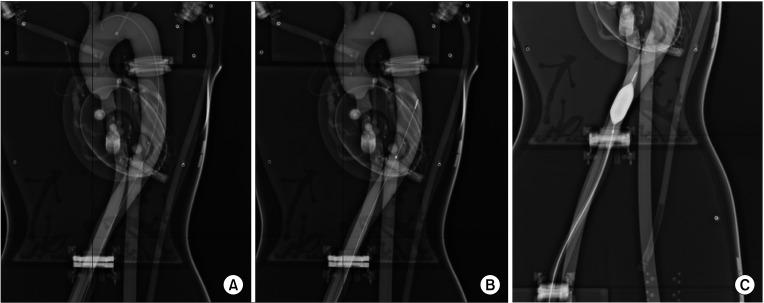

Resuscitative endovascular balloon occlusion of the aorta (REBOA) has emerged as a salvage technique changing the paradigm in the management of noncompressible torso hemorrhage. However, training for the REBOA procedure is rarely performed. The endovascular training for REBOA (ET-REBOA) course was conducted to develop the endovascular skills of participants.

METHODS

Sixteen residents and 12 specialists participated in this educational course. All participants were provided with precourse learning materials. The ET-REBOA course consisted of 2 sections; an ultrasound-guided sheath insertion on the puncture model, and a balloon manipulation on the vascular circuit model. A 13-item procedure checklist and the time required to perform the procedure were examined. Pre/post self-reported confidence score and course satisfaction questionnaire were obtained.

复苏性血管内主动脉球囊阻断术(REBOA)已成为一种挽救技术,改变了不可压缩性躯干出血的管理模式。然而,针对REBOA手术的培训很少进行。开展血管内REBOA培训(ET - REBOA)课程是为了培养参与者的血管内技能。

方法

16名住院医师和12名专科医生参加了这一教育课程。所有参与者都获得了课前学习材料。ET - REBOA课程包括两个部分:在穿刺模型上进行超声引导下的鞘管插入,以及在血管回路模型上进行球囊操作。检查了一份包含13项内容的操作清单以及完成操作所需的时间。获取了自我报告的课前/课后信心评分和课程满意度问卷。